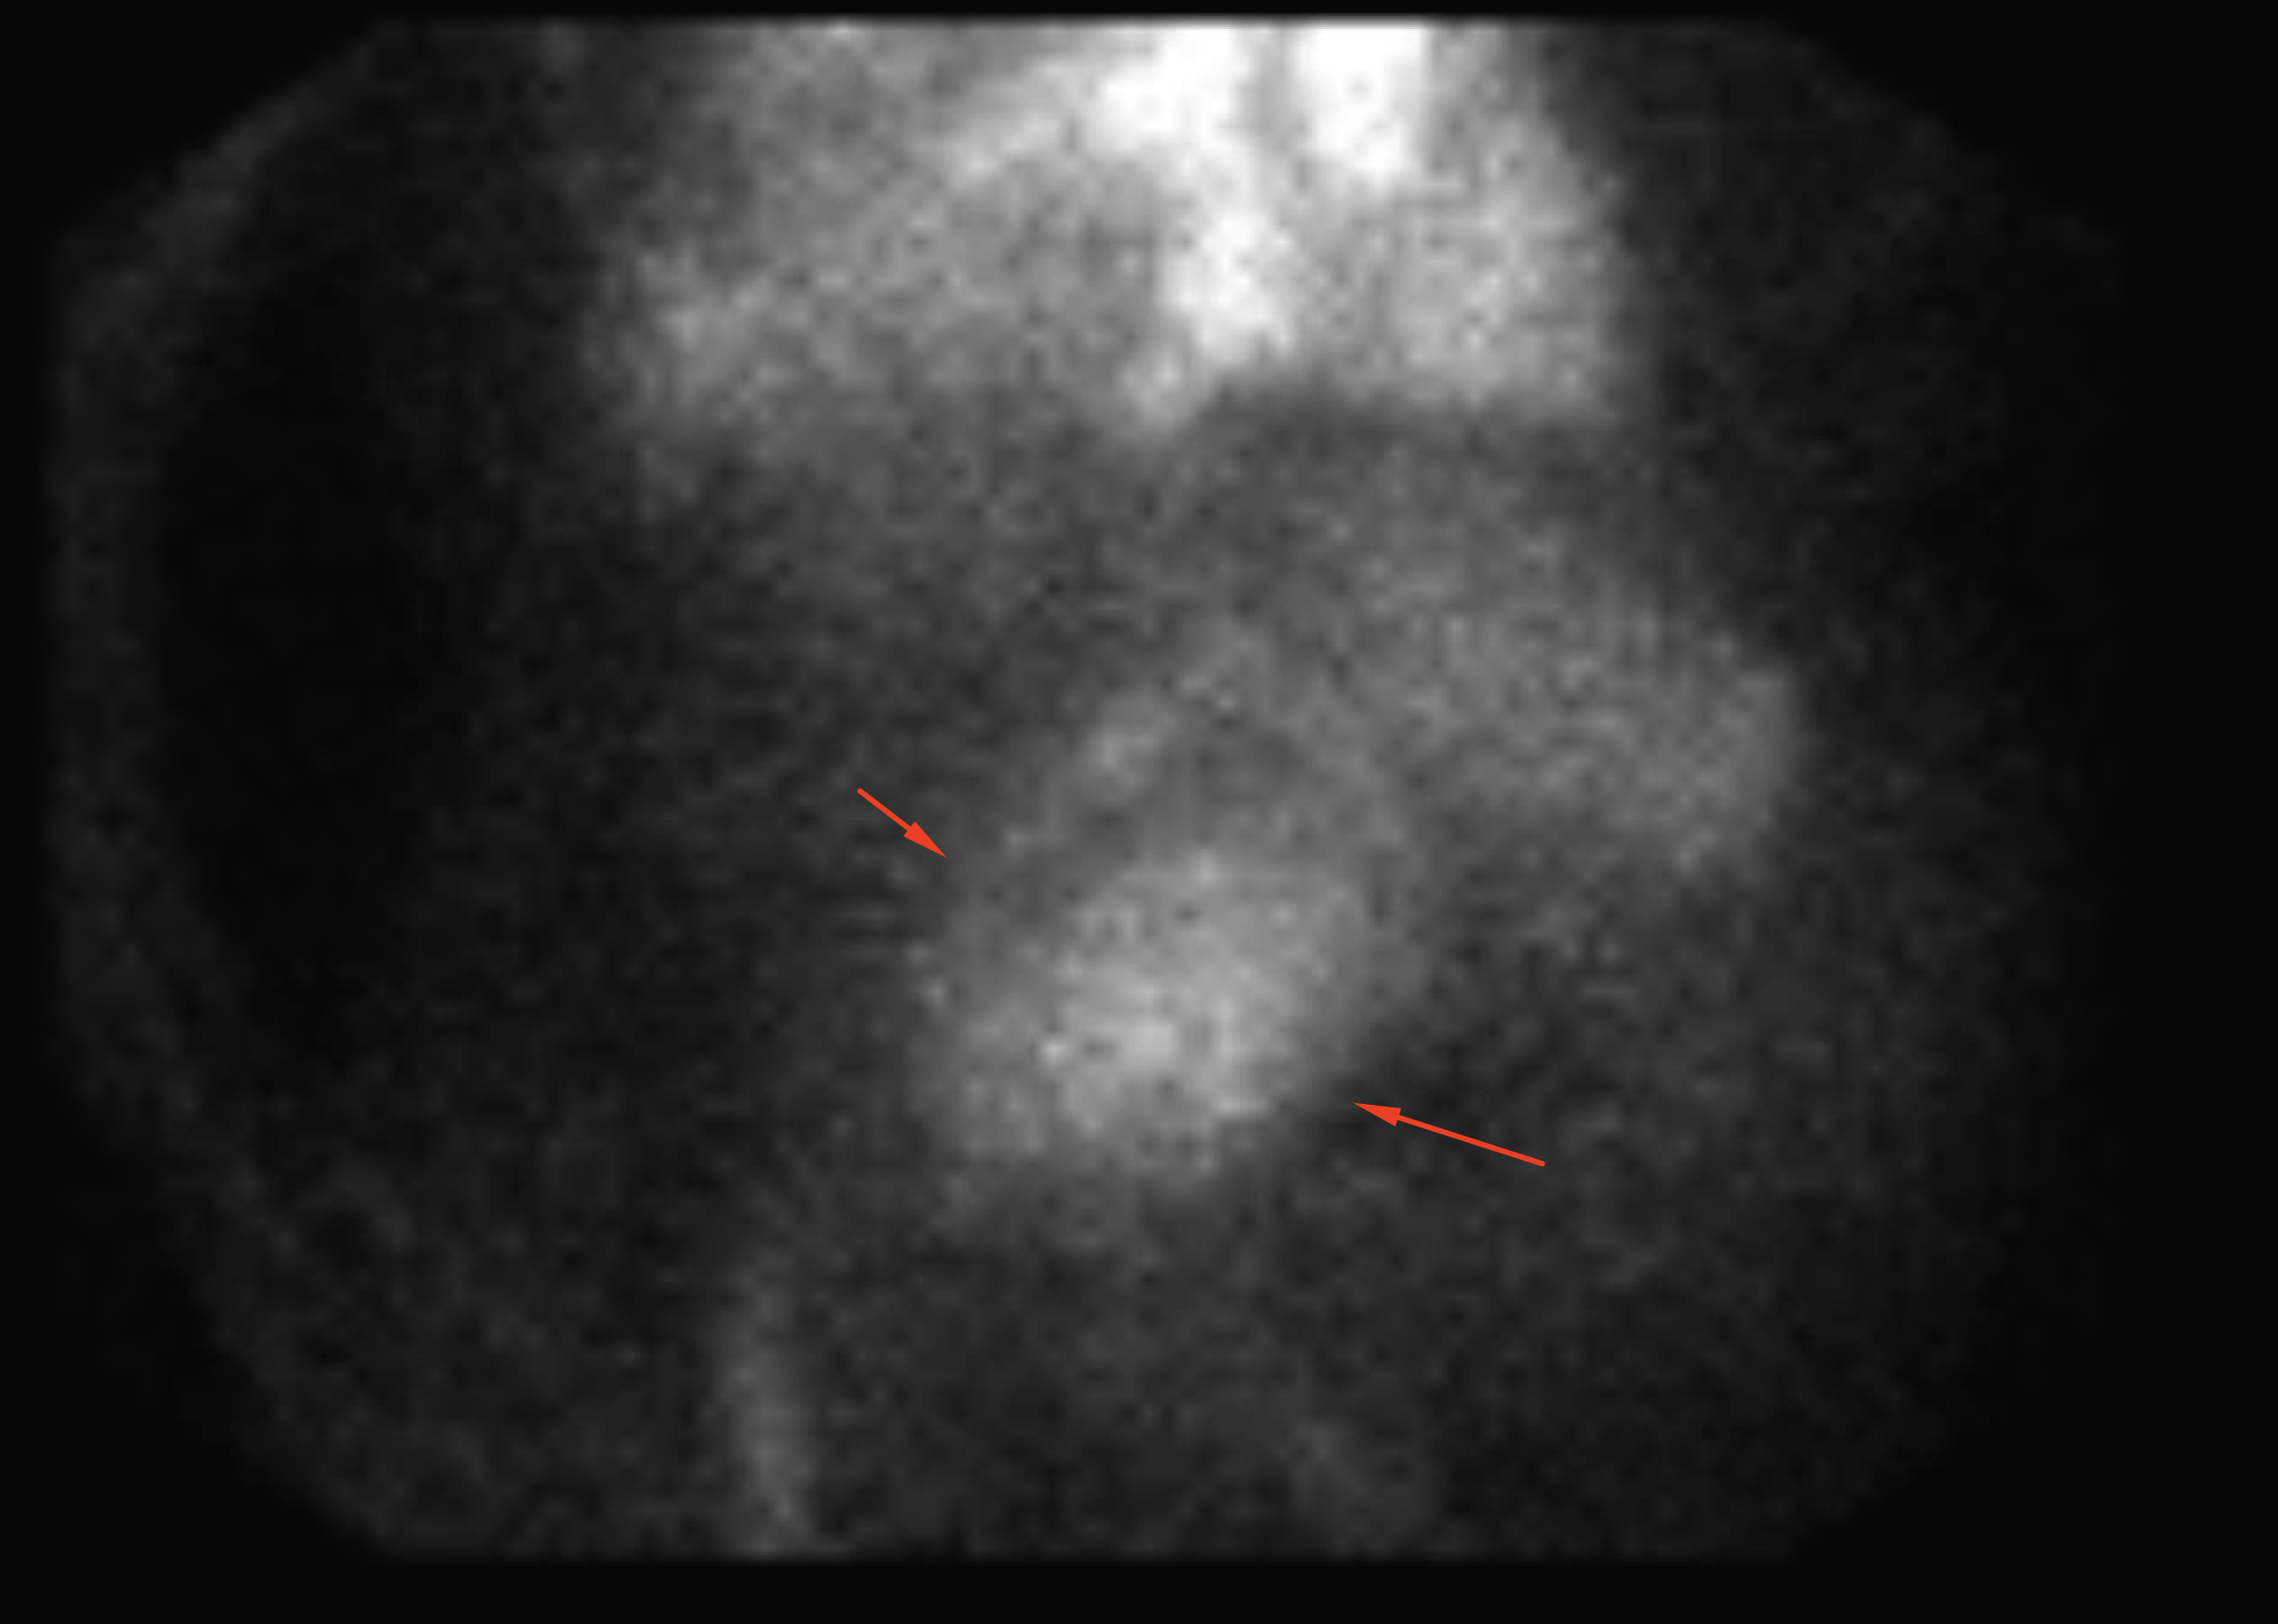

Age: 75

Sex: Female

Indication: Bright red blood per rectum, history of diverticulosis

Radiotracer: Tc99m labeled RBCs

Sample ReportNo evidence of active GI bleeding during the course of this exam.

Abdominal aortic aneurysm. Recommend CT or ultrasound for further assessment.